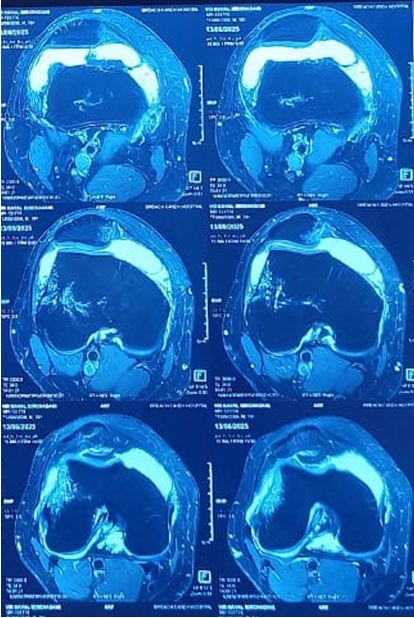

The patient was given a Long Knee immobilizer along with analgesics and was discharged home. He was advised to undergo an MRI of the right knee after 72 h once the swelling subsided. The MRI was done and along with the osteochondral defect and bony edema, the MRI showed a complete tear of the MPFL. Fig. 4,5

Figure 4: Magnetic resonance imaging of right knee – axial cuts.

Figure 5: Magnetic resonance imaging of right knee – coronal and sagittal cuts.

Another notable feature of our case is the patient’s generalized joint hypermobility (Beighton score 6/9), a known risk factor for patellar instability. Although the patient had no documented history of prior dislocations, his hyperlaxity may have contributed to the severity of injury from what appeared to be a single dislocation event. This raises the consideration that adult patients with constitutional ligamentous laxity may present with injury patterns more typical of adolescents. MRI imaging in our case provided essential insights, confirming the MPFL tear and identifying the precise size and origin of the osteochondral fragment. This influenced our decision to proceed with surgical management, balancing the need for articular surface preservation and patellar stabilization. While fragments smaller than 1 cm2 may be amenable to excision, larger defects–such as in our case measuring 2.5 × 2.5 cm–necessitate fixation to avoid long-term complications such as chondral degeneration or early osteoarthritis. In young patients, cartilage defects <1 cm2 can be left alone, especially if they are in the non-weight-bearing zone. In situations where the fragments are excised piecemeal/crushed or are larger than cm2 and are in the weight-bearing area of the femur, leaving the defect alone is not advisable. If the fragment is amenable to fixation, the best treatment option is fixation with headless screws/bio pins/or the newer suture tape devices, which are made of absorbable polygalactin 910. In cases where the fragment can not be fixed and the defect is in the weight-bearing portion of the joint or on the patella ridge, cartilage procedures are the treatment of choice. These can be done at the index surgery or can be done as a second stage (current recommendation). The defects can be filled with OATS, matrix augmented ACI. For chronic cases of osteochondral defects, the cartilage procedures have favourable outcomes [1,3,7].